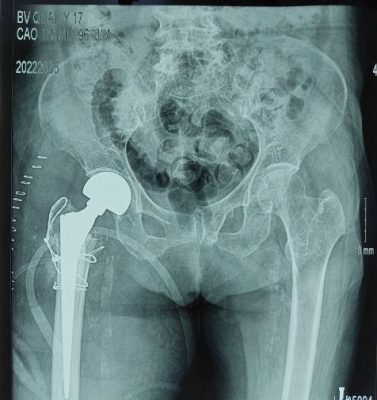

Gãy liên mấu chuyển xương đùi, mất vững Thay khớp háng gãy liên mấu chuyển xương

ở bệnh nhân cao tuổi, loãng xương nặng đùi, mất vững, ở bệnh nhân cao tuổi,

loãng xương nặng